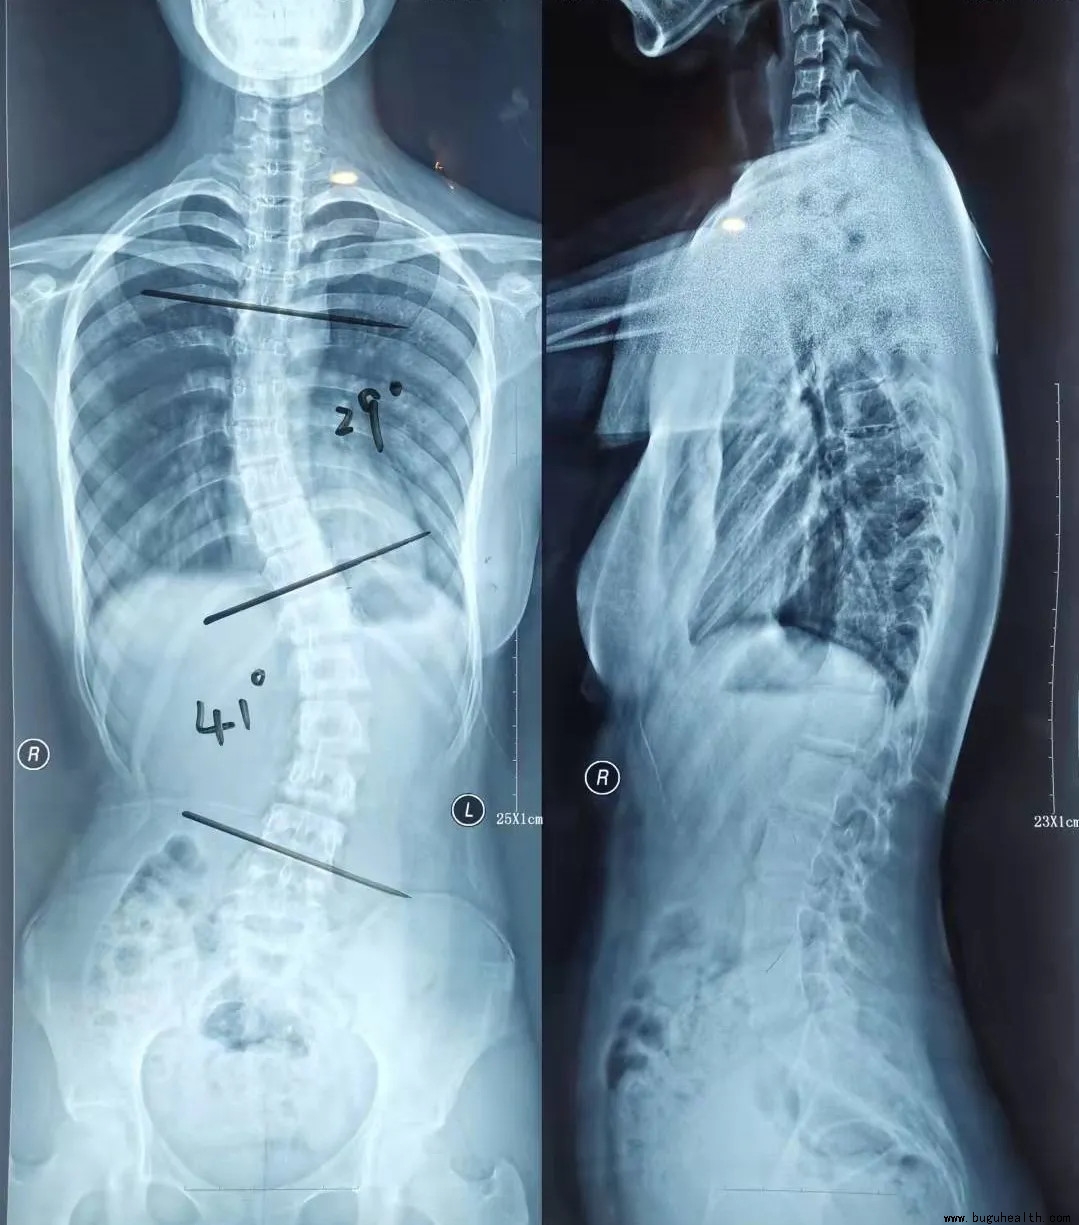

正常人的脊柱从正面或者背面看是直的,那么脊柱侧弯的患者如果检查脊柱全长X光片就会发现,自己的脊柱有了弯曲。为了便于观察侧弯畸形的进展及评估,著名的美国矫形外科医生John Robert Cobb教授(1903-1967)于1948年发明了简便实用的Cobb角测量法则,目前仍然是脊柱侧弯矫形医生最常用的方法:

1.此弯的上端及下端分别找到倾斜度最大的椎体,为上下端椎;

2.于上端椎的上缘,下端椎的下缘分别画平行线;

3.做两条平行线的垂线。

4.测量垂线的夹角。

简单来说就是4个步骤:上下端椎的选择,画平行线,做平行线的垂线以及角度测量;

测量结果:Cobb角<10°为阴性,10°≥Cobb角<20°为阳性,Cobb角>20°为明显阳性;即Cobb角>10°为脊柱侧弯。

注:画平行线时以椎体终板连线为准,如果X线片显示不清晰,此时常用椎弓根连线代替椎板连线;对于较大的侧弯,上述两平行线的交角亦等同于Cobb角。